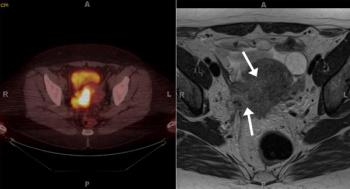

A 27-year-old man presents to his primary care physician, complaining of a palpable nodule in his right testicle. What is your diagnosis?